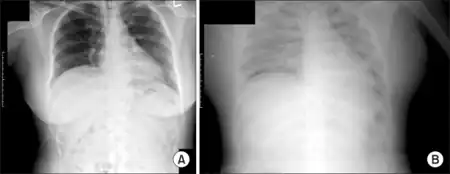

a) Normal chest x-ray b) capillary leak syndrome chest x-ray

SCLS is often difficult to recognize and diagnose on initial presentation, and thus misdiagnoses are frequent. The characteristic triad of profound arterial hypotension, hemoconcentration (elevated hematocrit, leukocytosis, and thrombocytosis), and hypoalbuminemia in the absence of secondary causes of shock and infection, requires diagnosis in a monitored, hospital setting during or after an acute episode. The fact that the condition is exceedingly rare – an estimated one per million inhabitants – and that several other diseases exhibit features akin to SCLS, including secondary capillary-leak syndrome or hypoproteinemia, militate against early identification.[2][7] Preserved consciousness, despite severe shock and hypotension, is an additional and most intriguing clinical manifestation often reported during episodes at hospital admission.[4]